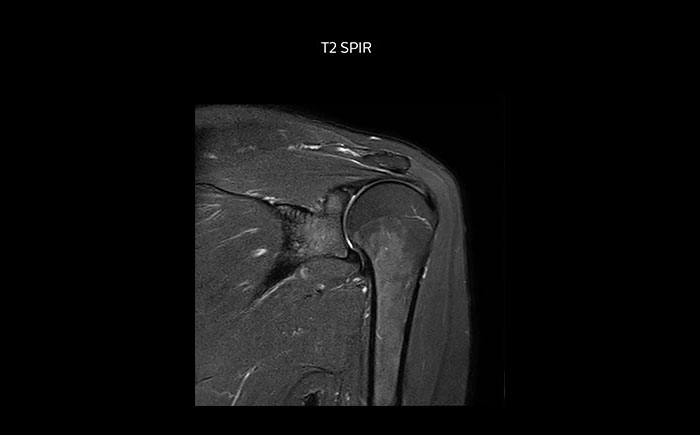

Shoulder MRI with high quality, large coverage

The Prodiva shoulder coil is very flexible and has large coverage, which makes good positioning easier, and that contributes to the superb image quality and high SNR that we get in our shoulder exams.

Shoulder MRI with high quality, T2 SPIR

Scan time 2:55 min, FOV 160 mm,

“The shoulder coil is a great example of easy positioning with Prodiva,” says Mrs. Maass “Other shoulder coils can be quite rigid, so that patients with pain, or bigger stronger shoulders, or a somewhat abnormal shoulder or spine anatomy cannot be positioned well in the coil, which often leads to loss of image quality. However, the Prodiva shoulder coil is very flexible and has large coverage, which makes good positioning easier and that contributes to the superb image quality and high SNR that we get in our shoulder exams.”